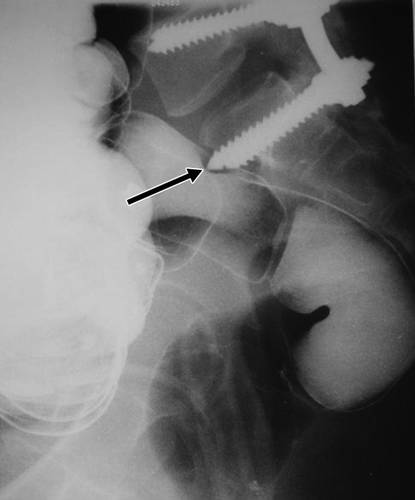

图7A-73岁的男子进行融合术后复查。侧位片显示螺钉断裂(箭头)。